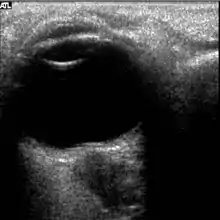

The astronauts affected by long term visual changes and prolonged intracranial hypertension have all been male, and SOS may explain this because in men, the sternocleidomastoid muscle is typically thicker than in women and may contribute to more compression. The reason that SOS does not occur in all individuals may be related to anatomic variations in the internal jugular vein. Ultrasound study has shown that in some individuals, the internal jugular vein is located in a more lateral position to Zone I compression, and therefore not as much compression will occur, allowing continued blood flow.

The first U.S. case of visual changes observed on orbit was reported by a long-duration astronaut that noticed a marked decrease in near-visual acuity throughout his mission on board the ISS, but at no time reported headaches, transient visual obscurations, pulsatile tinnitus or diplopia (double vision). His postflight fundus examination (Figure 1) revealed choroidal folds below the optic disc and a single cotton-wool spot in the inferior arcade of the right eye. The acquired choroidal folds gradually improved, but were still present 3 year postflight. The left eye examination was normal. There was no documented evidence of optic-disc edema in either eye. Brain MRI, lumbar puncture, and OCT were not performed preflight or postflight on this astronaut.[5]